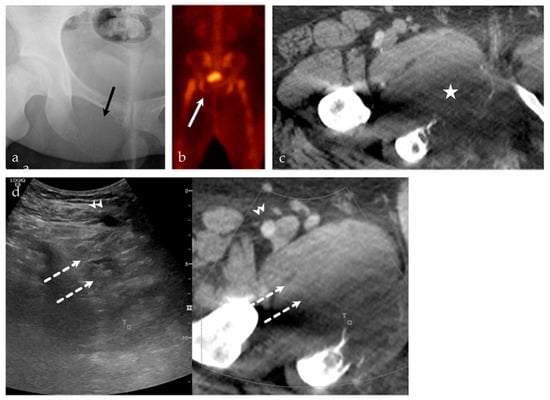

3.2.4. Targeted Percutaneous Lesion Biopsy and/or Aspiration

| NA **/F | Right psoas muscle | US-CT fusion | Abscess | Infection |

| 51/F | Left inferior pubic ramus | US-CT | Metastatic disease, breast carcinoma | Neoplastic, malignant |

| 24/M | Right inferior pubic ramus | US-CT | Ewing sarcoma | Neoplastic, malignant |